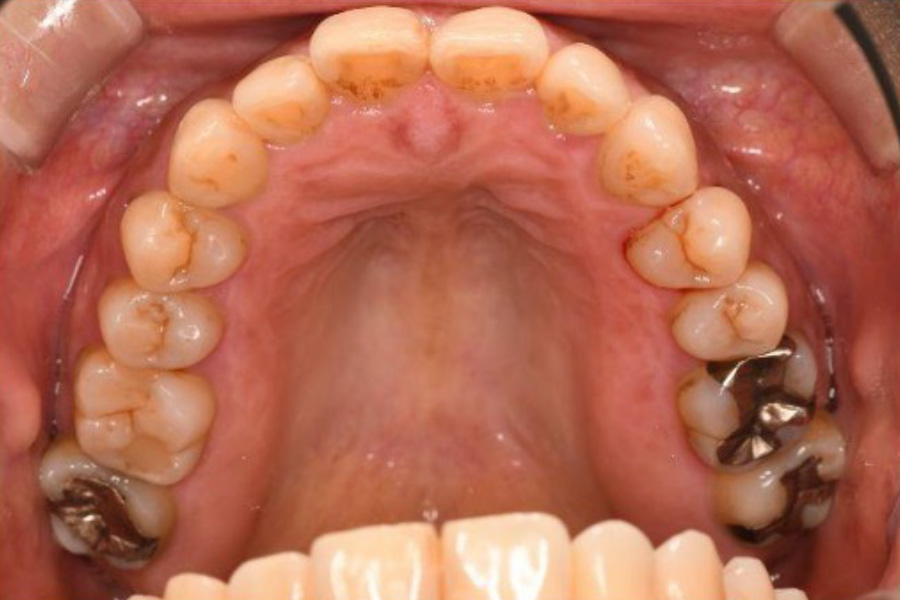

治療前

治療後

| 治療内容 | 全顎治療:歯周病治療、根管治療、 歯肉弁剥離掻爬術(フラップ手術)、 セラミック治療、ダイレクトボンディング |